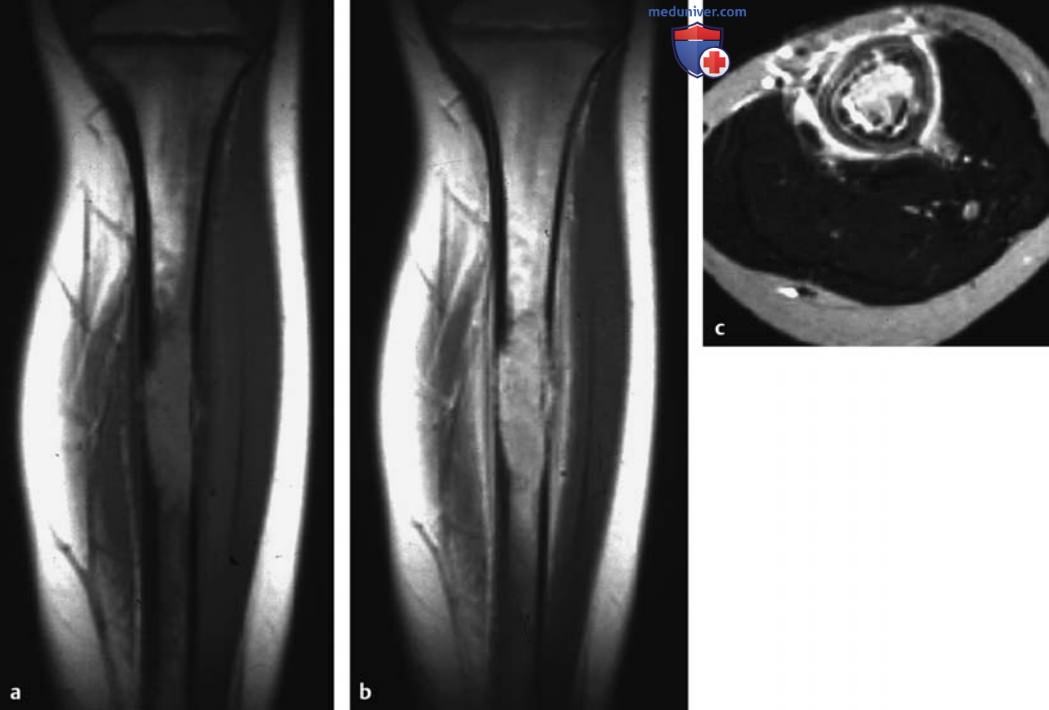

МРТ доброкачественных опухолей костей и опухолеподобных поражений

Рисунок 11. a-c Эозинофильная гранулема большеберцовой кости.

а Т1в-SЕ-изображение во фронтальной плоскости.

b Т1в-SE-изображение после контрастирования.

c Т2в-SЕ-изображение в аксиальной плоскости.

Обнаружено медуллярное поражение средней трети диафиза с перифокальным отеком костного мозга и отеком окружающих мягких тканей. Отмечаются заметное усиление сигнала в фокусе поражения после контрастирования, а также линейное усиление по ходу поверхности кости, обусловленное периостальной реакцией.